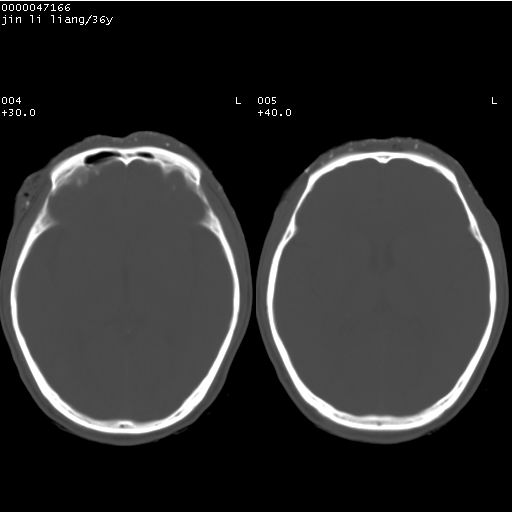

患者 男,36岁。头面部“土炮”炸伤。pe:面目全非,伤口流血不止。

临床诊断:头面部外伤。

颅脑ct轴位平扫(层厚、层距均为10mm),图像如下:

左眼球破裂并异物,眶周、额顶部头皮及软组织挫伤并异物

迎面一炮,满脸开曝。额顶部头皮及软组织挫伤并异物,左眼球破裂积气并异物,典型的面目全非,惨不忍睹。

额顶部头皮及软组织挫伤并异物,左眼球破裂积气并异物。可怜

1左侧眼球破裂并积气,球内、框内异物。

2额部顶部软组织伤。